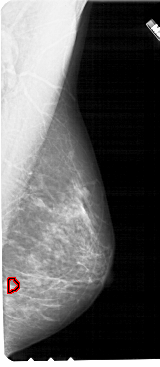

A_1715_1.LEFT_MLO

LEFT_MLO LINES 5491 PIXELS_PER_LINE 2536 BITS_PER_PIXEL 12 RESOLUTION 43.5 NON_OVERLAY